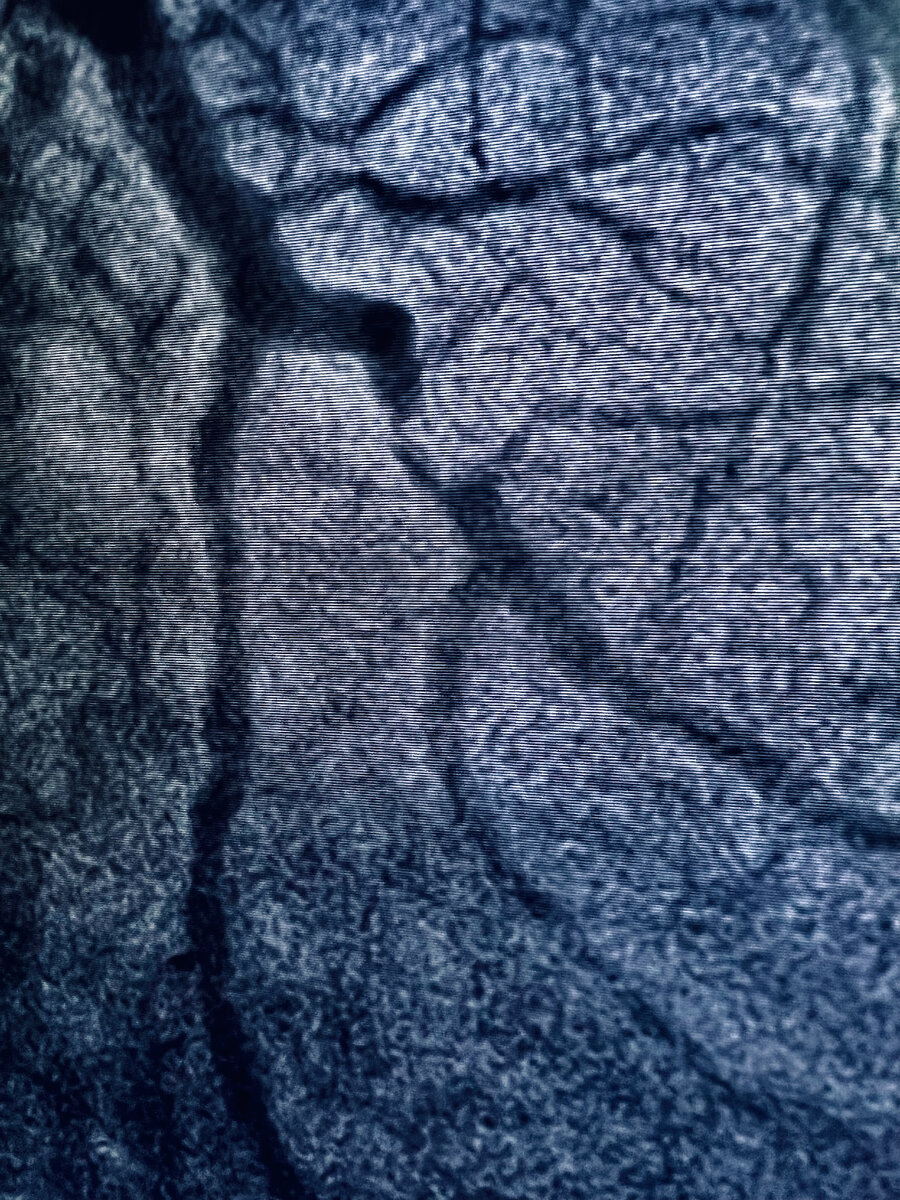

Одна из самых популярных процедур коронарография - метод визуализации коронарных артерий с помощью рентгенконтрастного вещества под рентгеновским излучением.